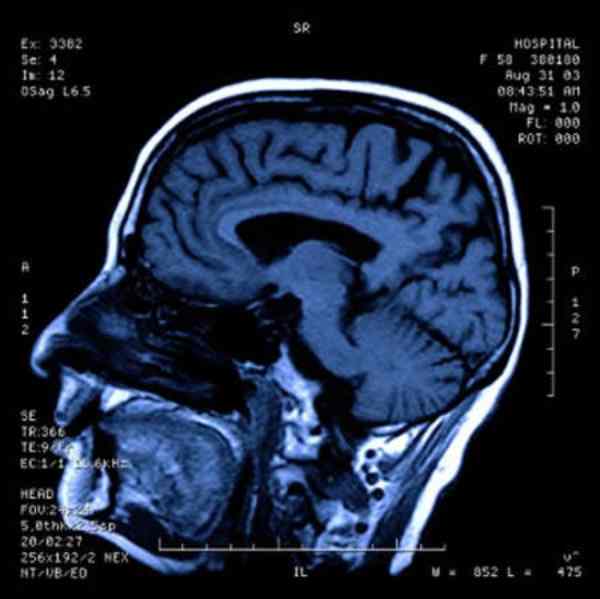

หลังจากอุบัติเหตุเฉียดตาย ชายคนหนึ่งนอนเป็นมนุษย์ผัก (ไร้ความรู้สึก) ไม่สามารถพูดคุย ขยับเขยื้อน หรือแสดงอาการเคลื่อนไหว ได้ วันหนึ่งในการทดลองกระตุ้นครั้งสุดท้ายแพทย์ได้สอด Electrodes เข้าไปที่ เนื้อสมองสีเทาที่ฐานของสมองใหญ่ (Thalamus) ที่ทำหน้าที่ตรวจจับการรับรู้และบริหารกลไกการเคลื่อนไหวภายในร่างกาย การทำครั้งนี้กลับเป็นการกระตุ้นที่จำเป็นต่อชายคนนี้ ทำให้เขาสามารถกลับมาพูดได้ ป้อนอาหารให้ตนเอง และพูดคุยกับครอบครัวได้